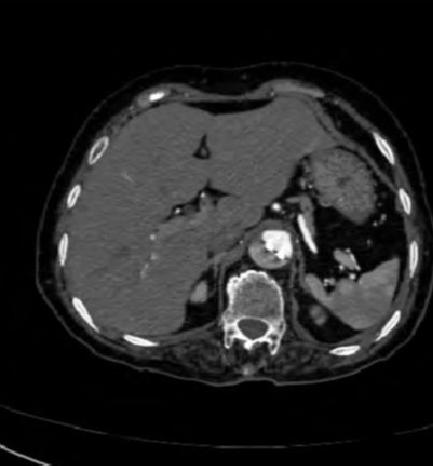

病例9

下面这个CT平扫,似乎有大问题!

图22

什么问题?似乎这里有大问题!

图23

同学,你眼神太好使了!

很可惜,这个不是问题,很多CT平扫都有这种线样阴影!

做个增强CT一看,哇,同学,你不光眼神好,运气也不是一般的好!

图24